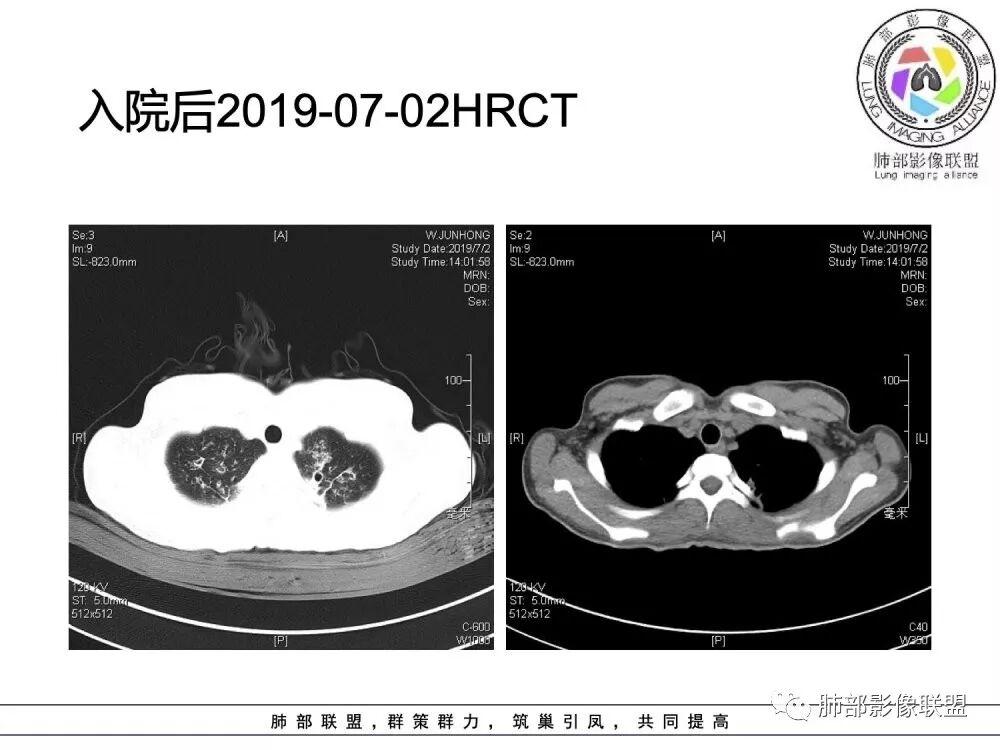

南边老师分析

这个病人15岁,病史10年,一直诊断支扩并感染,但是没提鼻窦病变;广泛支气管扩张,周围有伴随病灶,部分有钙化灶,肺气肿背景,首先是气道来源的病变,表现为:支气管壁增厚、支气管扩张、肺部感染;

(1)支气管壁增厚、支气管扩张

可广泛分布于两肺各叶,尤其是两肺上叶多见。支气管扩张主要是轻、中度柱状支气管扩张。支气管壁增厚既可发生于扩张的支气管,也可发生于非扩张的支气管,常为轻度增厚,管壁内外比较光滑。

(2)两肺弥漫性肺气肿

表现为肺野密度低而不均,在不同病例病变程度轻重不一,婴儿或儿童患者多见。

(4)薄壁含气囊腔

因支气管扩张、气肿性肺大泡及间质性气囊肿形成大小不一之囊腔,与支气管相关。

(5)斑片状阴影

表现为感染性支气管肺炎和亚段肺不张。呈1~3cm大小不等的斑片状高密度影,上肺野常见或上肺野病灶分布较多。